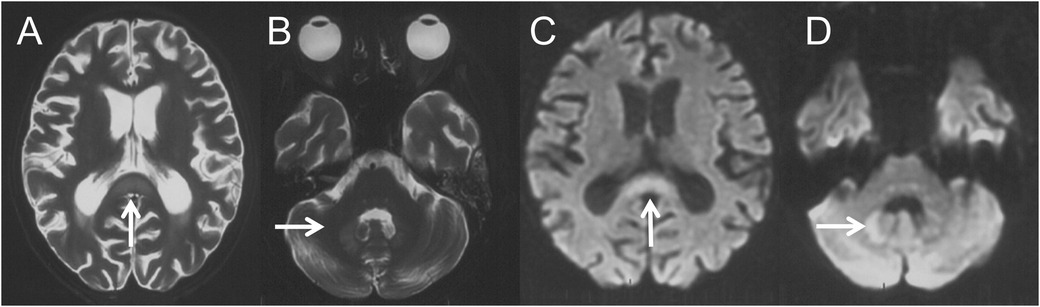

A 13-year-old female was diagnosed with AML-M2 at the age of 10. She underwent two Allo-HSCTs, 2 years and 5 months before the current presentation, respectively. After the second transplant, she developed intermittent diarrhea with occasional pseudomembranous stools, prompting clinical suspicion of CDAD. Intravenous metronidazole therapy was initiated at 7.5 mg/kg every 6 hours and continued for 39 days (cumulative dose: 31.2 g). Forty-four days after discontinuation, recurrent diarrhea prompted re-initiation of metronidazole at the same daily dose. After 47 days of continuous metronidazole therapy (cumulative dosage 37.6 g), she developed irritability, dysarthria, and involuntary movements including tongue protrusion, blinking, and grimacing. Brain magnetic resonance imaging (MRI) performed 4 days after symptom onset demonstrated cerebral atrophy and symmetrical lesions in the splenium of the corpus callosum and dentate nuclei with T1-weighted (T1W) hypointensity and T2-weighted (T2W)/fluid-attenuated inversion recovery (FLAIR)/diffusion-weighted imaging (DWI) hyperintensity (Figure 1). Brain MRI prior to the first metronidazole course was normal. Electroencephalography revealed a fast background rhythm with scattered multifocal sharp waves. Cerebrospinal fluid (CSF) analysis was normal. Laboratory tests indicated alanine aminotransferase 45 IU/L (normal range 9–50 IU/L), aspartate aminotransferase 64 IU/L (15–40 IU/L), total bilirubin 57.4 μmol/L (1.7–20 μmol/L), and direct bilirubin 29.4 μmol/L (0–6 μmol/L). The symptoms deteriorated gradually with lethargy, aphasia, dysphagia, dystonia, urinary retention, external ophthalmoplegia and chemosis.

Figure 1. Four days after the onset of MIE, brain MRI revealed symmetric lesions with hyperintensities on axial T2W (A,B) and DWI (C,D) images over the splenium of corpus callosum (A,C, thin arrows) and dentate nucleus (B,D, thin arrows).